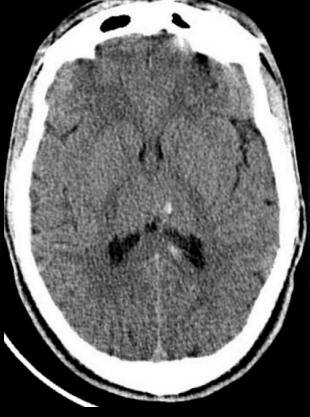

Injuria axonal difusa

se puede observar una pequeña zona de hemorragia a nivel del tallo cerebral.